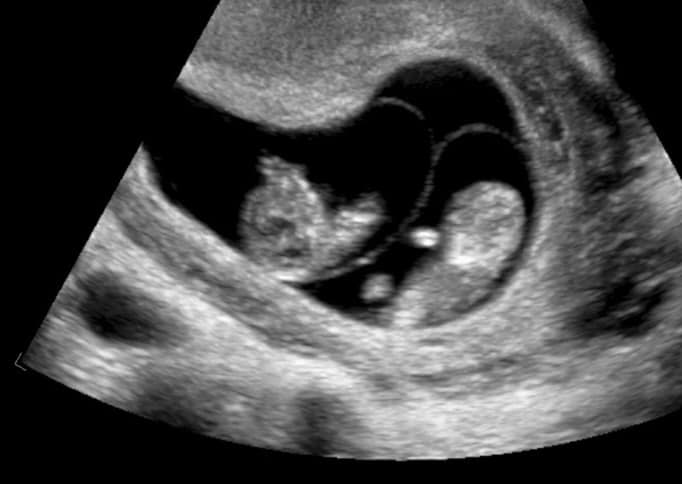

像第二張圖在高解析度超音波下你看到的就是單絨毛膜雙羊膜(看不懂沒關係等你當婦產科醫師我就會教你)